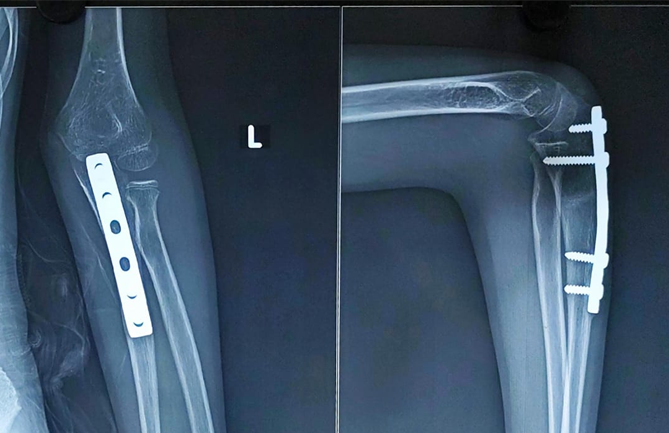

Surgical intervention was planned to restore normal elbow anatomy and function. Under general anesthesia and with tourniquet control, the child underwent open reduction and internal fixation of the ulna with distraction angulation ulnar osteotomy to correct the angulation and length. Across a Boyd approach (Fig. 2), an overcontoured AO 3.5 mm small fragment DCP was used to stabilize the ulnar osteotomy and to ensure proper alignment through which the radial head reduced spontaneously (Fig. 3).

Figure 3: Immediate post-operative X-ray showing reduced radial head with ulnar osteotomy site fixed with AO 3.5 mm small fragment DCP plate.